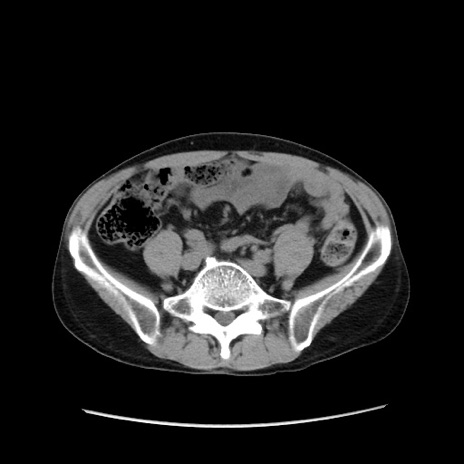

症例37(横断像)

【症例】40歳代 男性

【主訴】腹痛

【現病歴】4時間ほど前に電車に乗車中に臍部上より腹痛出現。徐々に増悪し起立困難となり、救急外来受診。生ものは数日食べていない。今朝お雑煮を食べた。

【身体所見】BT 36.8℃、BP 117/84mmHg、HR 91/min、SpO2 97%、苦悶様、腹部:臍上部広範囲圧痛あり、反跳痛±

【データ】WBC 8100、CRP 0.03